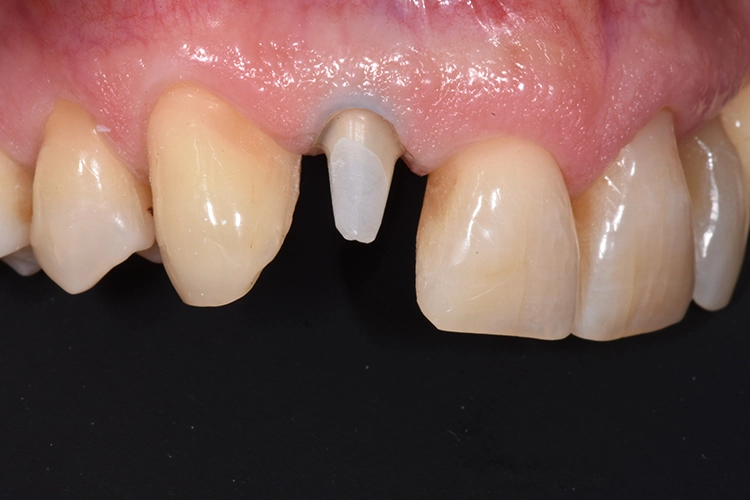

Anschließend wurde der durch die externe Resorption stark angegriffene Wurzelrest schonend entfernt. Bei der Sofortimplantation kommt es auf den Erhalt der lokalen knöchernen Bedeckung an.

Die Alveole wird von Granulationsgewebe gesäubert und direkt postoperativ durch ein Kleinröntgen auf Wurzelreste kontrolliert. Die Aufbereitung des Implantatbettes und die Implantatinsertion erfolgt im apikalen Bereich tendenziell eher palatinal. Im Bereich der Implantatschulter wurde ein Abstand von 2,5 mm zur vestibulären Lamelle eingehalten.

Aufgrund der Angulation der Implantate im Frontzahnbereich steht man mit einem verschraubten Provisorium oftmals vor dem Problem des vestibulär durchtretenden Schraubenkanals. Dieses Problem lässt sich mit dem iSy System elegant umgehen.

Die erste Verbindung dient ausschließlich der dreidimensionalen Fixierung in Relation zum Abutment. Die weitere Ausarbeitung der Krone erfolgt extraoral, wobei auf die Gestaltung eines physiologischen Emergenzprofils geachtet werden muss. Anschließend wird das Provisorium einfach auf die Implantat-Basis geklickt, das Bild zeigt die Situation unmittelbar nach der Implantation (Abb. 23-28).